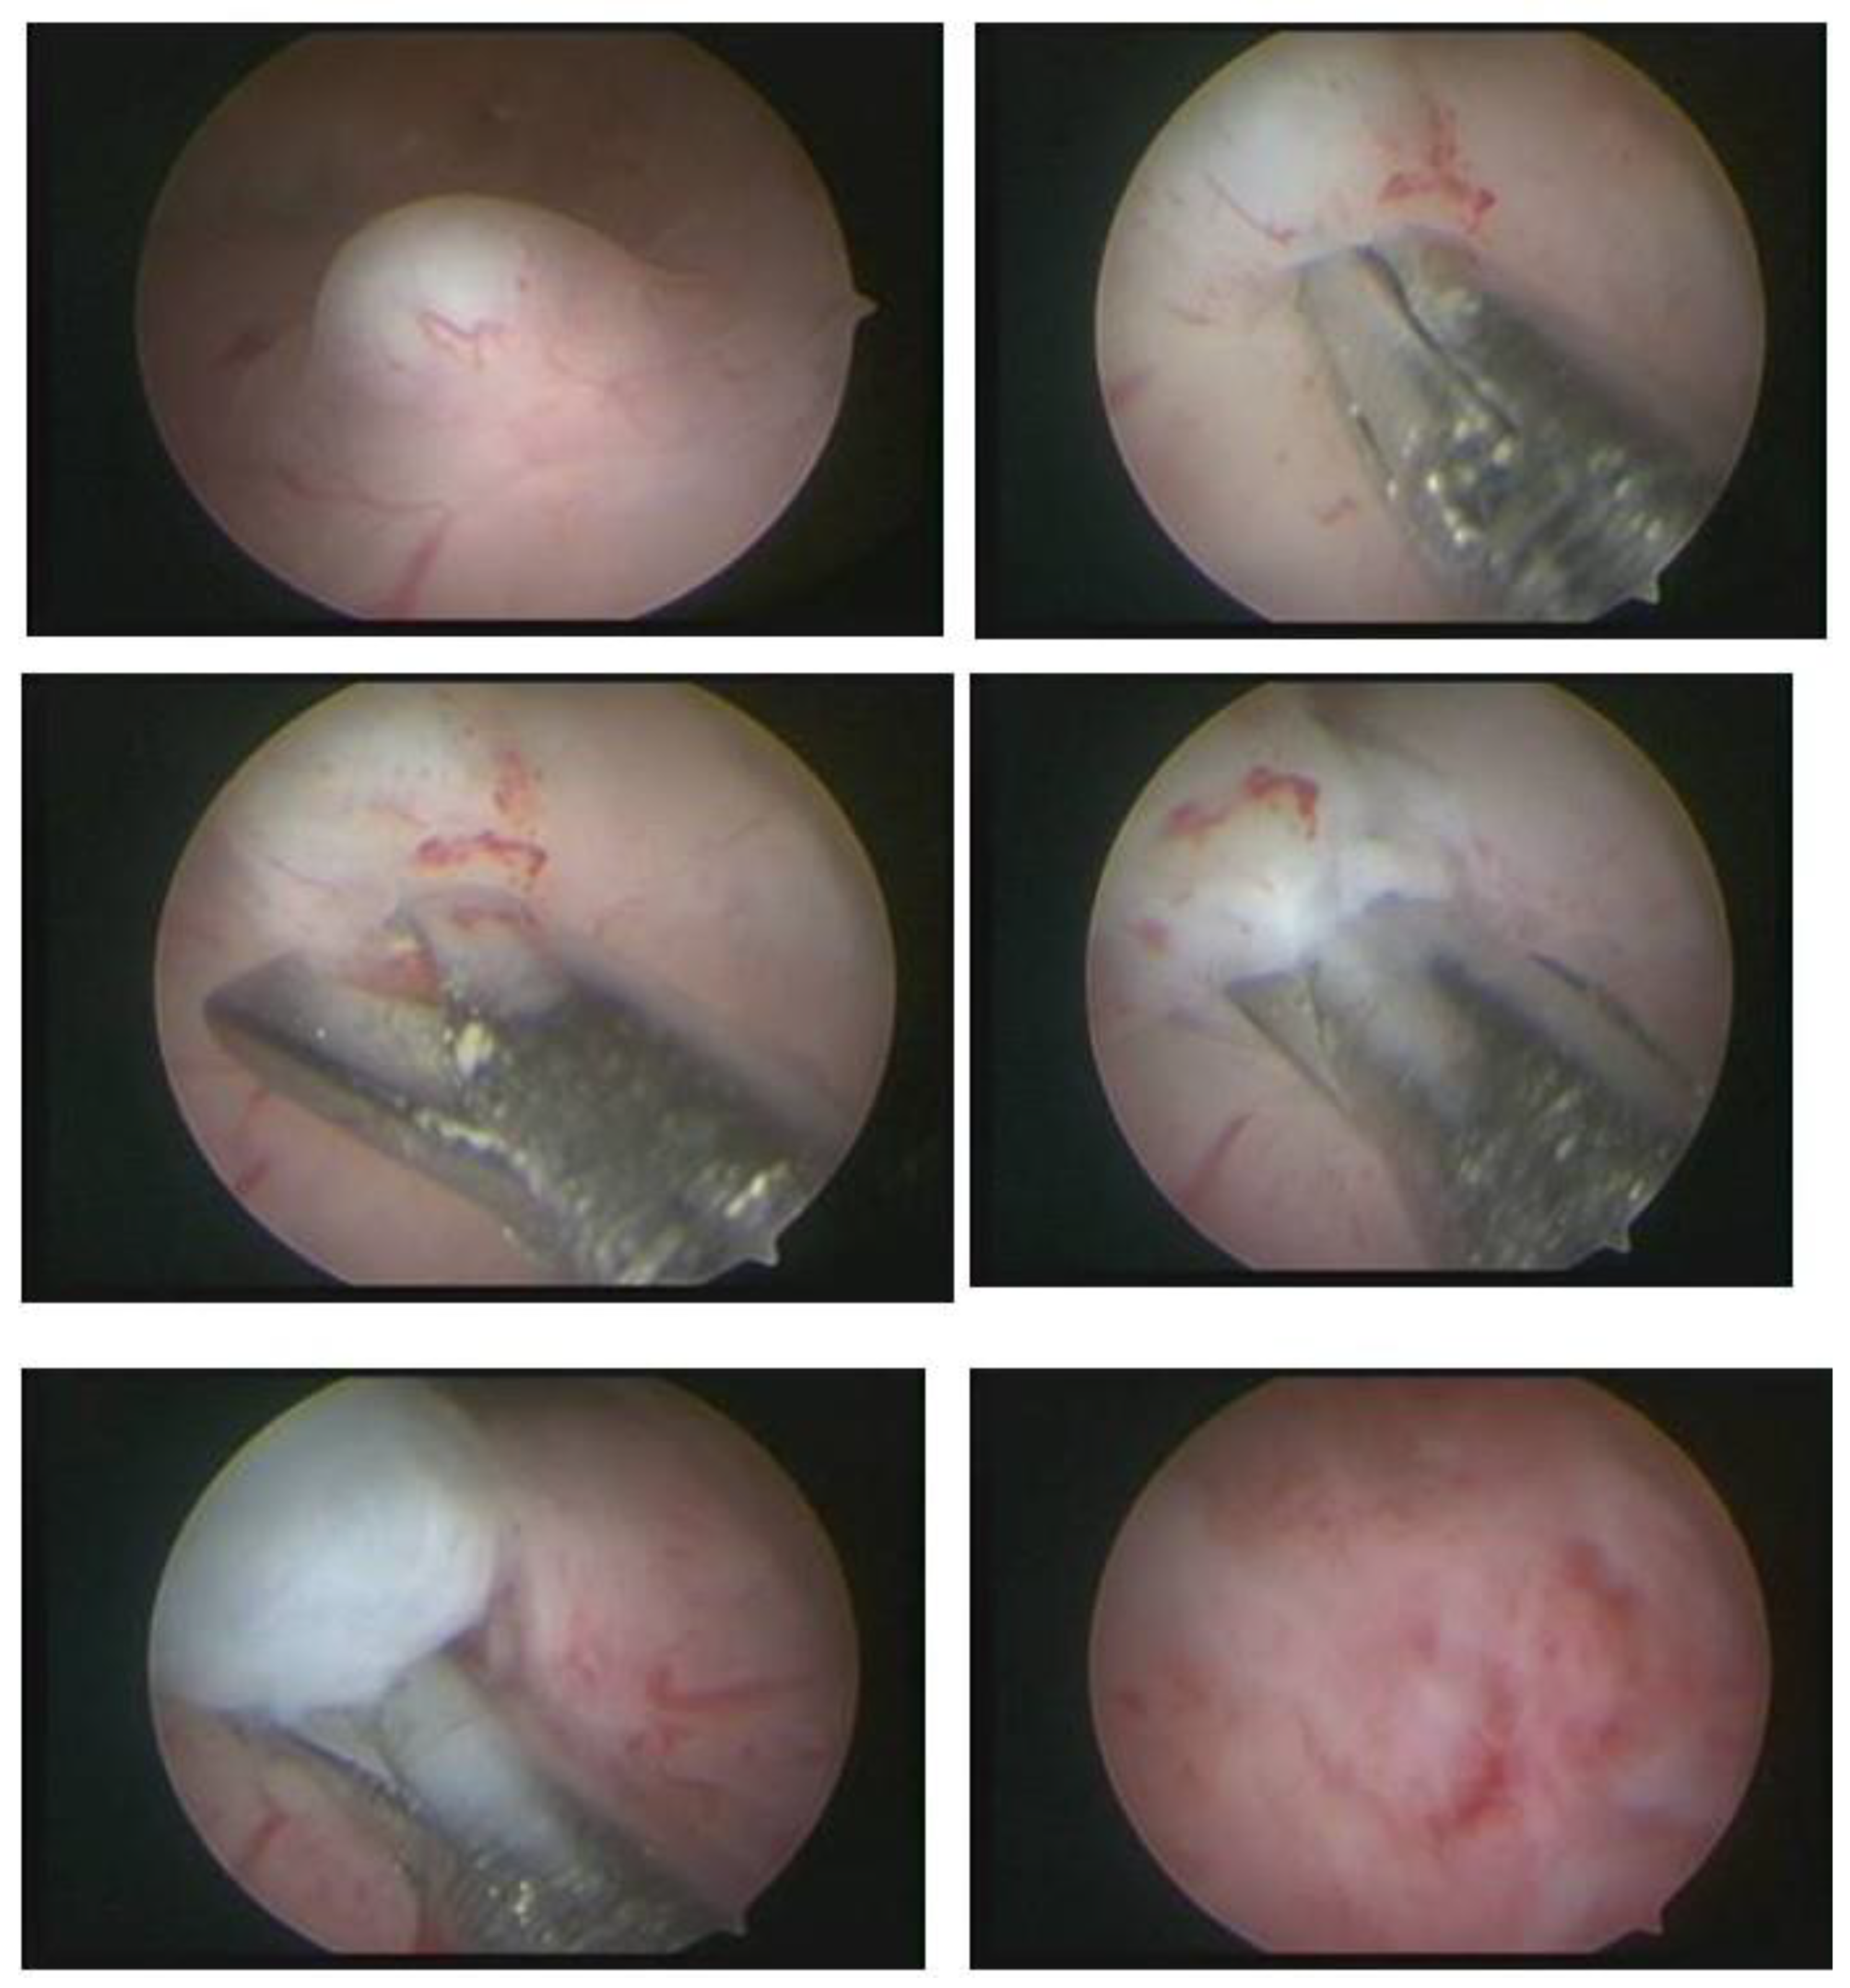

The technique with the resectoscope, regardless of the type of energy, is the same, with planned loop movements always in the fundus–cervical direction, with the angulation of the resectoscope axis to define the degree of resection depth. These two movements have to be thought out and prepared before activating the energy so that only the myoma is resected, avoiding resection of the myometrium and the risk of perforation, and so that the penetration of the cut is as desired, without risk (Figure 9).

The movement of the resection loop with energy can only be moved in the fundus–cervix direction, but, without energy, it can be driven in any direction, even the cervix–fundus, as it will have mechanical action. This nonenergy loop movement, called a cold loop, is often used to mobilize and enucleate the submucosal fibroid.

3.8. Mazzon’s Cold Loop Technique

Mazzon’s technique was described in 1995 and is based on the resection of the submucosal component of the myoma using a resectoscope with a semicircle loop, with mono or bipolar energy, until reaching the intramural portion of the myoma. Upon reaching the pseudocapsule, the loop is changed to a more rigid one, which is not energized (cold loop), so that the myoma is mechanically mobilized until its enucleation. Then, a loop with energy returns to fragment and remove the myoma, which was left free in the uterine cavity. It has the advantage of approaching the myometrium without current, with lower risk of perforation and lower risk if perforation happens (thermal injury to other organs), with less thermal damage to the myometrium, less bleeding, and less intravasation [34] (Figure 13).

3.9. Mobilization and Enucleation Technique Using the Pseudocapsule—Lasmar

The technique published by Lasmar in 2002 has the name of “direct mobilization of the myoma”. It consists of incising the endometrium around the submucosal myoma using the resectoscope with the Collins loop until reaching the pseudocapsule, releasing the existing fibrous beams. Once the pseudocapsule is identified, with the same instrument, a movement similar to that performed in laparotomic and laparoscopic myomectomy is performed, separating the myoma from the myometrium in its entirety, causing it to slide into the myometrium.

As there is no traction, as in abdominal surgery, the base of the fibroid is released, starting at the lateral edges, entering with the Collins loop in the cervix–fundus direction without energy at the same time as slight mobilizations in the fibroid are made with the resectoscope assembly. The Collins loop is kept moving from the lateral to the central part of the myoma, parallel to the nodule and moving it with the hysteroscope, leading the myoma to progressively migrate to the uterine cavity until its complete release from the uterine wall. This is facilitated by the decompression of the myometrium, which, compressed by the growth of the nodule, progressively returns to its normal position by releasing the pseudocapsule, causing the intramural lesion to become intracavitary. This technique, like all those that perform myoma enucleation, has the same advantages: lower risk of perforation and risks associated with perforation (thermal injury to other organs), less thermal damage to the myometrium, and less bleeding and intravasation [35].

With the myoma totally in the cavity or almost totally, the nodule is sliced, using the Collins loop, in the longitudinal direction to remove it in large fragments, improving efficiency (Figure 14).

Figure 13. Mazzon technique with “cold loop”.

Figure 14. OR hysteroscopic myomectomy, with Collins electrode, enucleation, and preserving pseudocapsule.